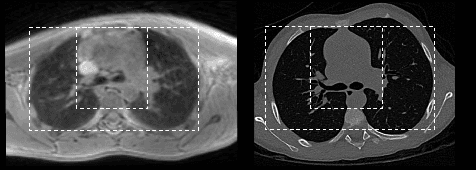

Abstract:Medical image synthesis generates additional imaging modalities that are costly, invasive or harmful to acquire, which helps to facilitate the clinical workflow. When training pairs are substantially misaligned (e.g., lung MRI-CT pairs with respiratory motion), accurate image synthesis remains a critical challenge. Recent works explored the directional registration module to adjust misalignment in generative adversarial networks (GANs); however, substantial misalignment will lead to 1) suboptimal data mapping caused by correspondence ambiguity, and 2) degraded image fidelity caused by morphology influence on discriminators. To address the challenges, we propose a novel Deformation-aware GAN (DA-GAN) to dynamically correct the misalignment during the image synthesis based on multi-objective inverse consistency. Specifically, in the generative process, three levels of inverse consistency cohesively optimise symmetric registration and image generation for improved correspondence. In the adversarial process, to further improve image fidelity under misalignment, we design deformation-aware discriminators to disentangle the mismatched spatial morphology from the judgement of image fidelity. Experimental results show that DA-GAN achieved superior performance on a public dataset with simulated misalignments and a real-world lung MRI-CT dataset with respiratory motion misalignment. The results indicate the potential for a wide range of medical image synthesis tasks such as radiotherapy planning.